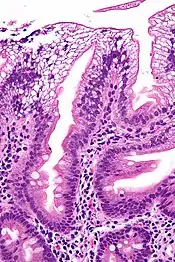

| Micrograph showing enterocytes with a clear cytoplasm (due to lipid accumulation) characteristic of abetalipoproteinemia. Duodenal biopsy. H&E stain. | |

There is an absence of apolipoprotein B. On intestinal biopsy, vacuoles containing lipids are seen in enterocytes. This disorder may also result in fat accumulation in the liver (hepatic steatosis). Because the epithelial cells of the bowel lack the ability to place fats into chylomicrons, lipids accumulate at the surface of the cell, crowding the functions that are necessary for proper absorption.